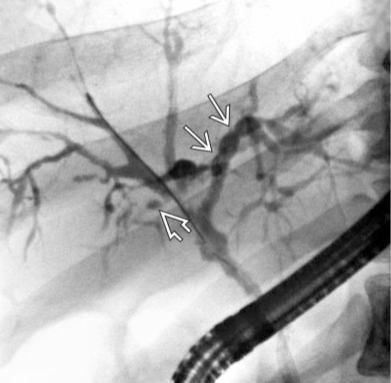

ERCP (endoscopic retrograde cholangiopancreatography)

With endoscope, cannulate duodenal papillae and view biliary & pancreatic tree

If stones present, can be removed

Allows treatment at same time as dx

Often done intraoperatively during a lap chole

Potential complication: Pancreatitis

MRCP or endoscopic US can be done first for dx, only doing ERCP if needed for stone removal

ERCP

Common Bile Duct Stones